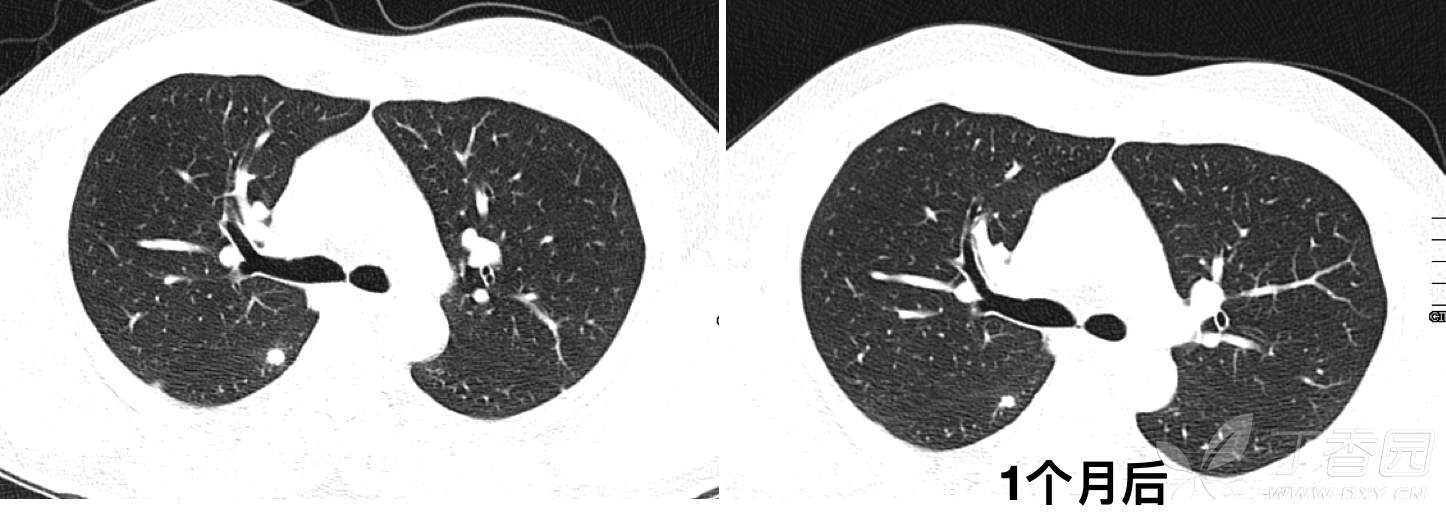

CT发现右肺多发结节影,初步诊断为肺炎,予莫西沙星口服治疗2周,1个月后复查CT如下: